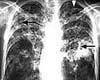

Leicester Scientists Seek To Disarm TB's Molecular Weapon

Leicester, UK (SPX) Mar 10, 2008

Scientists at the University of Leicester are claiming a new advance in their fight against the resurgence of TB in Britain. They have isolated the molecular 'weapons' of the bacterium and are now assessing ways to make the bacterium impotent.